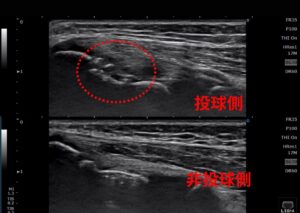

当院では初検時に必ず超音波エコー観察を実施します。 今回のケースでも、レントゲンだけでは判断が難しい微細な変化を可視化しました。

- エコー所見: 肘の内側上顆(骨端線が閉じていない成長期特有の骨端核部分)に、明らかに問題がある像を確認。

- 可視化のメリット: 「どこが、どう悪いのか」を選手本人と親御さんがモニターで一緒に確認することで、「なぜ休まなければならないのか」「どうすれば治るのか」という納得感が生まれます。